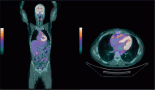

At this point, to reduce the continuous pain and the decreased vision, we started treatment with cyclophosphamide (500 mg/w i.v. for three consecutive weeks and one of suspension), lenalidomide [10 mg/daily orally days 1–21 every 28 days], and dexamethasone (40 mg intravenously, days 1–2, 8–9, 15–16) (L-CD) [6, 7].

After the first cycle, the exophthalmos, periorbital oedema, conjunctival hyperaemia, diplopia, and continuous pain disappeared (Figures 3 and 4).

Figure 3: The exophthalmos, periorbital oedema, conjunctival hyperaemia disappeared after first cycle of therapy.

When the extramedullary relapse the percentage of bone-marrow plasma cells was <5%, with monoclonal IgG < 1 g/dl. Therefore, we decided to start a new combination of treatment, based on lenalidomide. To attain a quicker response, this treatment was supplemented with dexamethasone and cyclophosphamide.